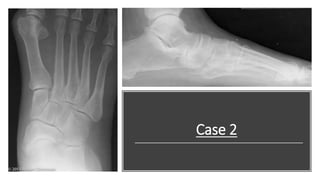

This is DP view of the right foot. Accessory

navicular type 3 noted. The is an increase in

talocalcaneal and cuboid abduction angles; The

forefoot adduction angle is decreased.

Talonavicular joint "congruency" is less than

75%.

Note: When are working up a flat foot patient, only address

pertinent angles based on the patient presentation and history. Do

not start with 1st MPJ and bunion angles.

Yes!! The patient has a severe bunion deformity BUT you are

working her up for flat foot. So stick to that.

You can vaguely address that “Bunion deformity is noted” so they

know that you know.

This is a lateral view of the right foot. I see a decrease in

calcaneal inclination angle and 1st metatarsal

declination angles. The talar declination angle is

increased. The cyma line is "broken" anteriorly. Ankle

joint looks congruent. No significant signs of arthritis

noted.

Diagnosis: Pes planus/ Kidner foot (based upon DP

view findings).